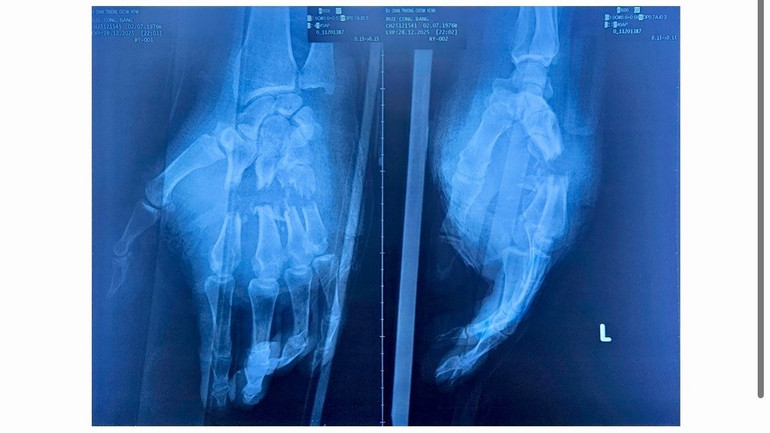

Hình ảnh chụp phim cho thấy nhiều xương ngón tay bị gãy hở.

Sau khi được sơ cứu ban đầu, bệnh nhân được chuyển đến Bệnh viện Chấn thương chỉnh hình Thành phố. Qua thăm khám, cho thấy vết thương kéo dài từ mặt lòng đến mặt lưng bàn tay, gãy hở nhiều xương bàn ngón, đứt toàn bộ gân, mạch máu và thần kinh của bốn ngón tay, các ngón tím lạnh, mất hoàn toàn vận động và cảm giác.